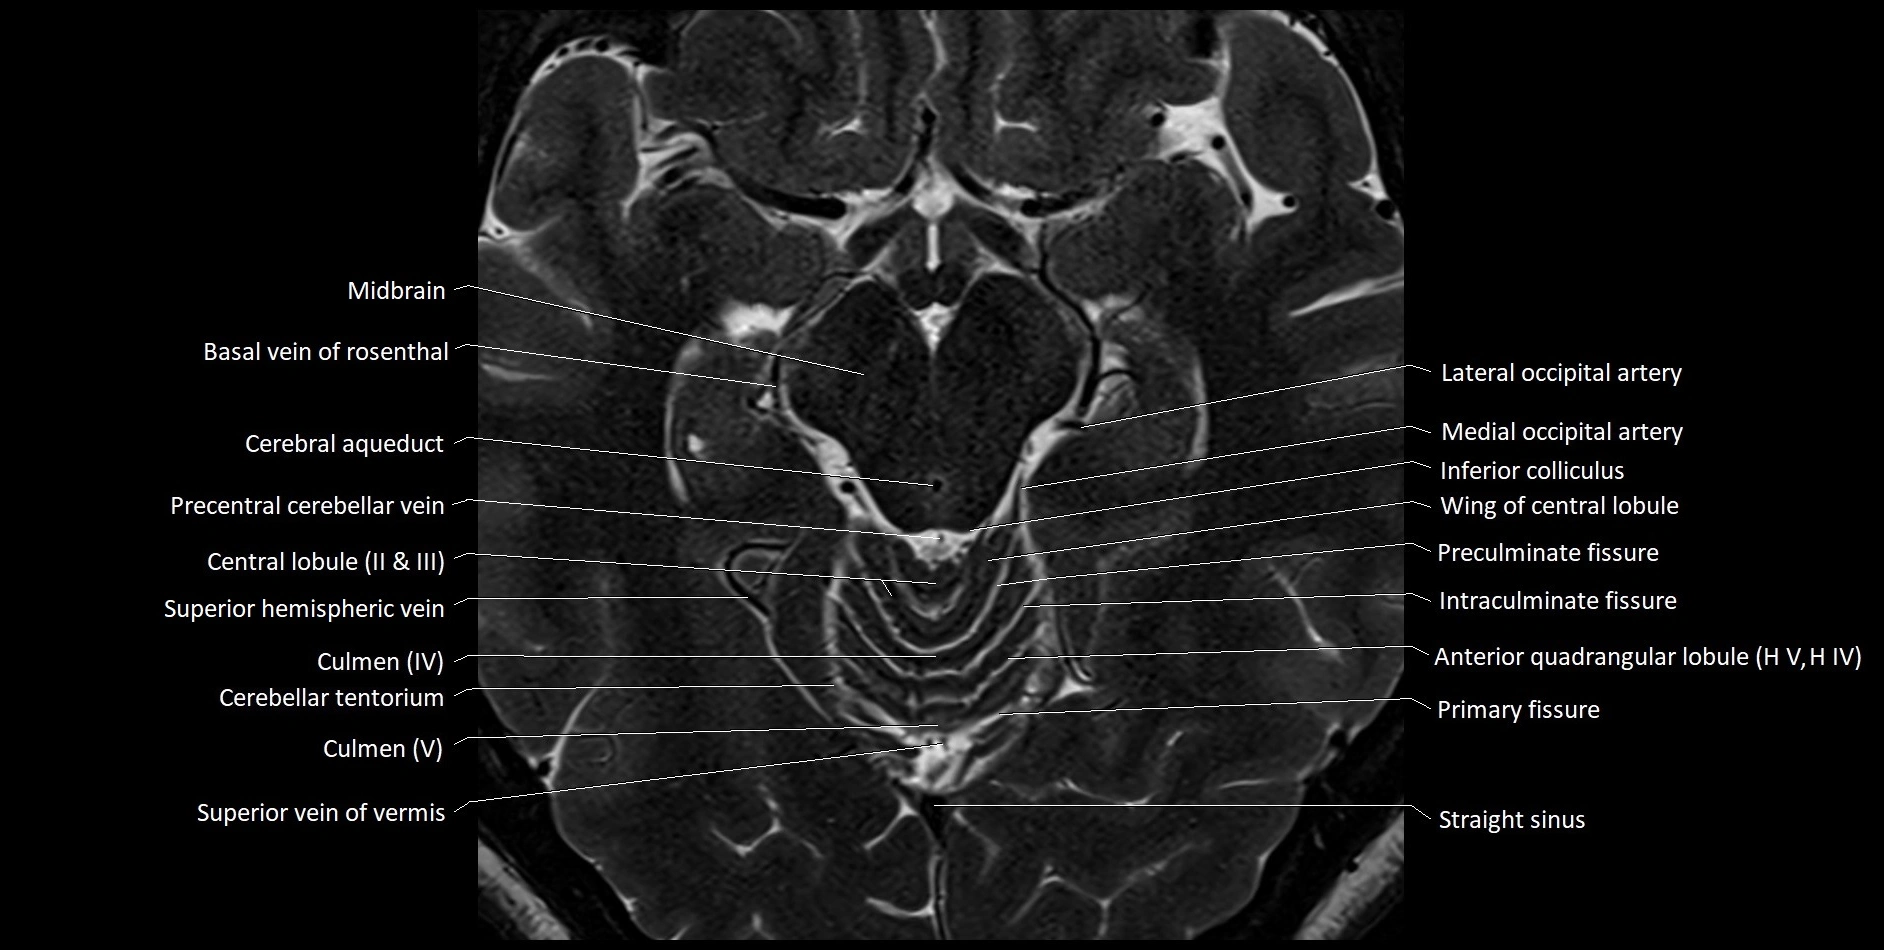

MRI images